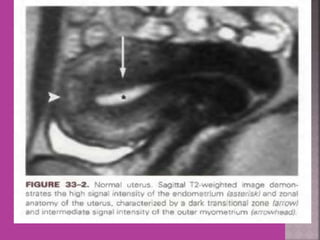

 Study of normal uterus and adnexa – with

aim to have clear image of normal

myometrium, endometrium , ovary and

follicles within the ovary.

Uterus

Cervix

Vagina

Rectum

Sacrum

Normal- Uterus

Uterus Cervix Vagina Rectum Sacrum